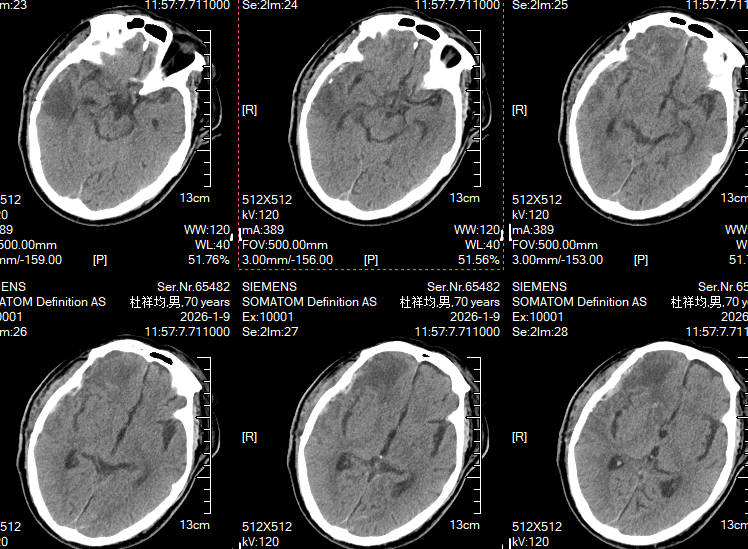

患者入院时已处于深昏迷状态,无自主呼吸,血压持续偏低,需依靠大剂量升压药维持;右侧瞳孔散大,提示脑疝形成,同时伴有严重创伤性休克、血氧饱和度仅82%,肋骨及骨盆多发骨折、双侧血气胸和腹腔脏器损伤等多系统损伤。神经外科重症监护室立即开启创伤救治绿色通道,在积极进行重症支持的同时,迅速完成相关检查与评估。

入院时颅脑CT平扫显示,多发脑挫伤